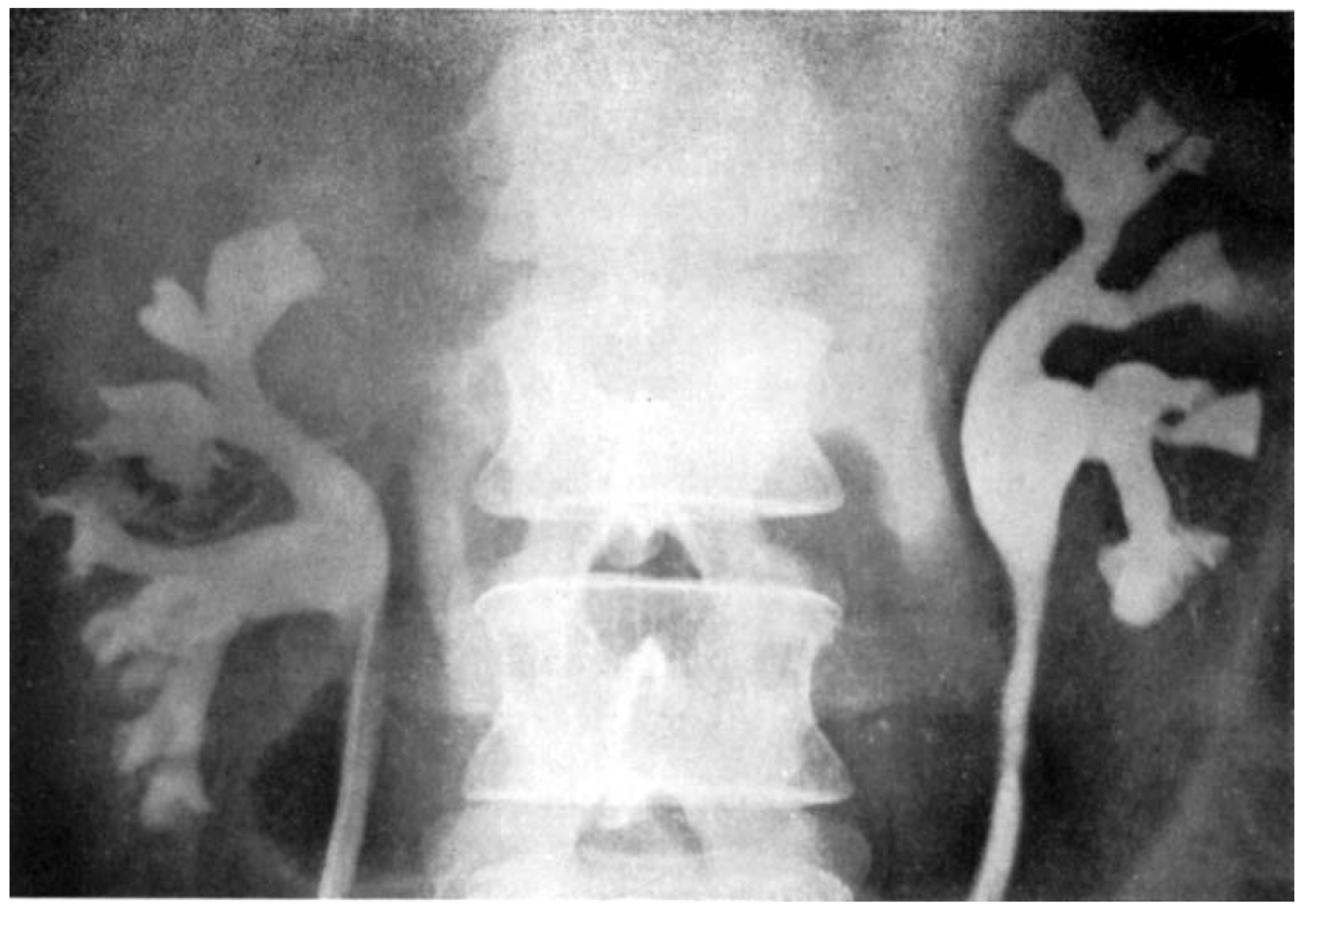

Pyelorenal Backflow

Backflow of contrast material from collecting system into renal or perirenal spaces. Usually caused by increased pressure in collecting system from retrograde pyelography or ureteral obstruction.

(lymphatic type)

https://www.tandfonline.com/doi/pdf/10.3109/00016925309175821